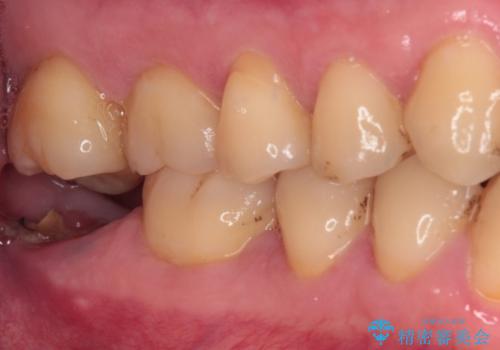

- 左下欠損部のインプラント治療を希望して来院された患者様です。

左下の欠損部を長期間欠損を放置していたことで、咬み合う上の奥歯が動いてしまっていたので、まずは上顎奥歯の部分矯正を行うこととしました。

理想的な咬み合わせに改善した上で、インプラント補綴治療を行うこととしました。